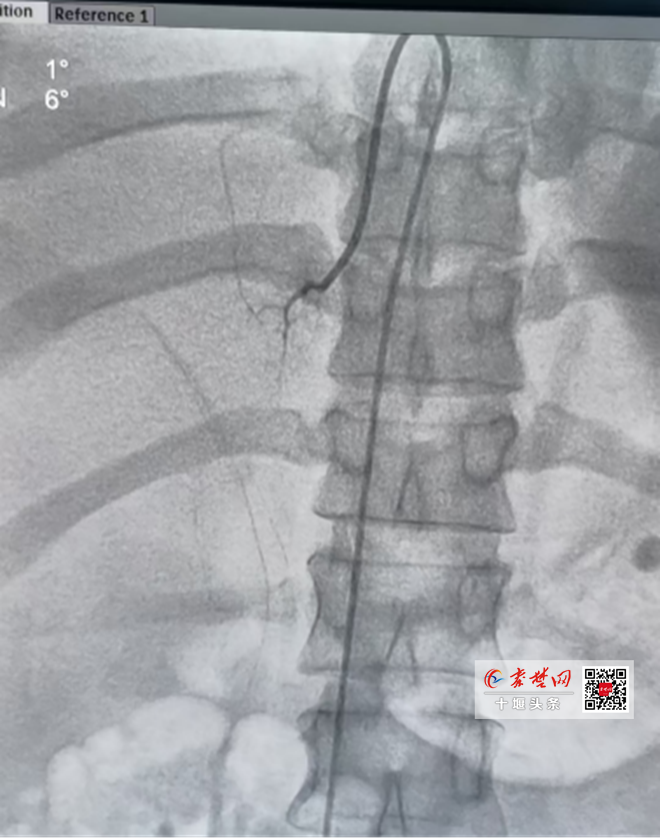

据赵继先主任介绍,该技术采用微创介入技术,通过股静脉,对患者双侧肾上腺中心静脉分段采血,更能直接、准确测定醛固酮、肾素等肾上腺激素局部水平。但在介入过程中,由于肾上腺静脉较为细小、解剖变异多,难度大,对操作者的介入技术要求相当高,并且需要非常丰富的介入手术技巧才能完成。

手术由沈俊博士、夏南博士、曾海星主治医师组成介入团队成功实施,过程顺利。术后ARR证实患者为原发性醛固酮增多症,患者虽然双侧肾上腺有结节,但是左侧肾上腺醛固酮分泌为右侧80倍,左侧肾上腺为醛固酮分泌优势侧。下一步,手术团队拟对患者左侧肾上腺结节采取微创手术。

沈俊博士介绍,肾上腺静脉取血术(AVS)是一种微创的介入检查手段,是原发性醛固酮增多症定位诊断的 “金标准”。它不仅能够精准判断患者是否有醛固酮增多症,还能精确诊断哪一侧肾上腺是优势分泌侧,为精准治疗以及后续手术的精准定位提供保障,有效避免误切非优势侧肾上腺,确保手术质量。接受 AVS 指导下的肾上腺手术的患者,高血压有望治愈,从而摆脱终身服药的困扰。